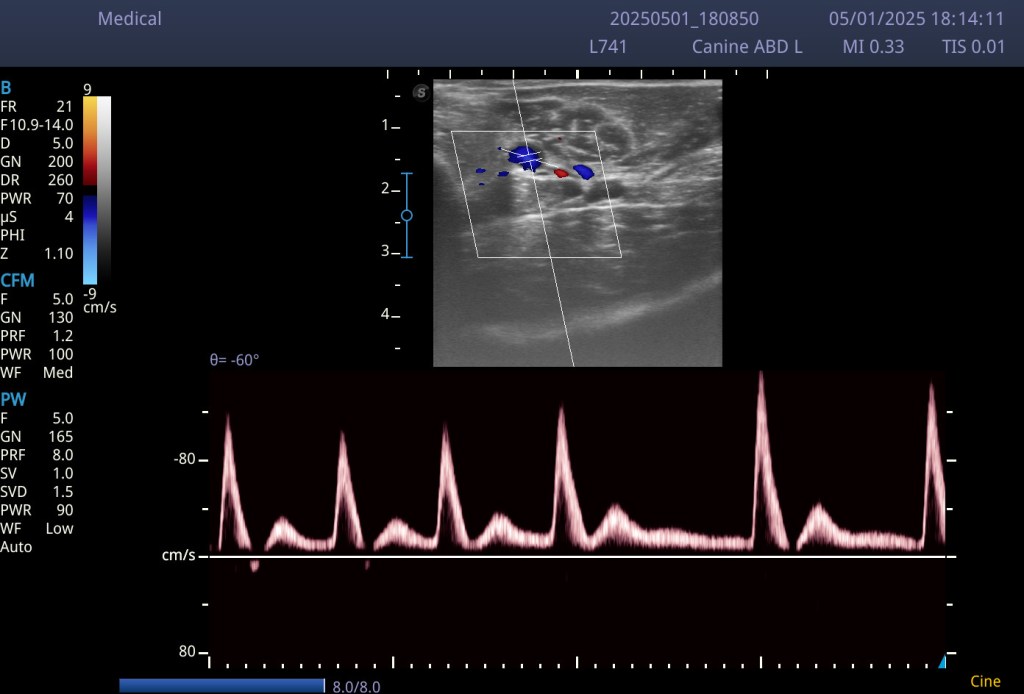

En la imagen que te compartimos hoy, puedes ver una representación muy clara:

- 🔴 Las arterias son pulsátiles, es decir, su pared se mueve rítmicamente con el latido cardíaco. Tienen una pared gruesa, su forma suele mantenerse redondeada y el flujo se puede visualizar con un patrón pulsado en Doppler.

📸 Imagen educativa:

Arteria